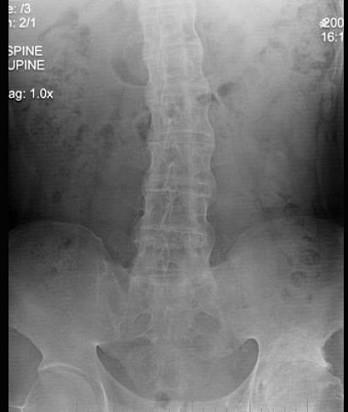

问题 41岁男性患者,发现腰部酸肿不适10多年,近来年感病情加重,腰部活动受限,晨起腰部僵直1年,行腰椎正侧位摄片如图示,最佳的诊断是 ( )

选项 A、斯梯尔综合征 B、化脓性脊柱炎 C、弥漫性骨质增生症 D、强直性脊椎炎 E、腰椎退行性变

答案 D